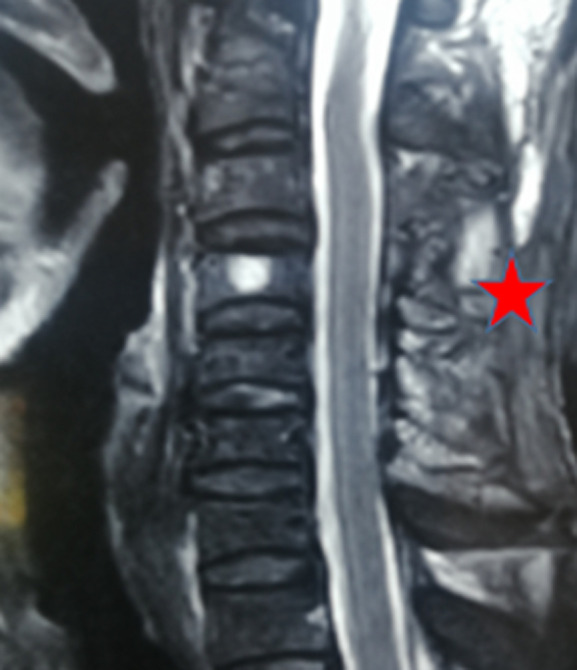

Post-traumatic spinal epidural cervical hematoma is defined as a collection of blood at the level of the epidural space following a trauma. It remains a rare presentation. We report here the case of a cervical epidural hematoma extending from C3 to C5, in a 55-year-old patient victim of a public traffic accident admitted one hour after trauma. Computed Tomography (CT) scan found a compressive epidural hematoma extending C3 to C5; the patient underwent a posterior surgical approach, which allowed to evacuate the hematoma. This rare clinical entity is an emergency diagnosis and management, which needs collaboration between, Intensive Care Unit (ICU) specialists, neurosurgeons, neuroradiologists, and physiotherapists for good outcomes and follow-up.